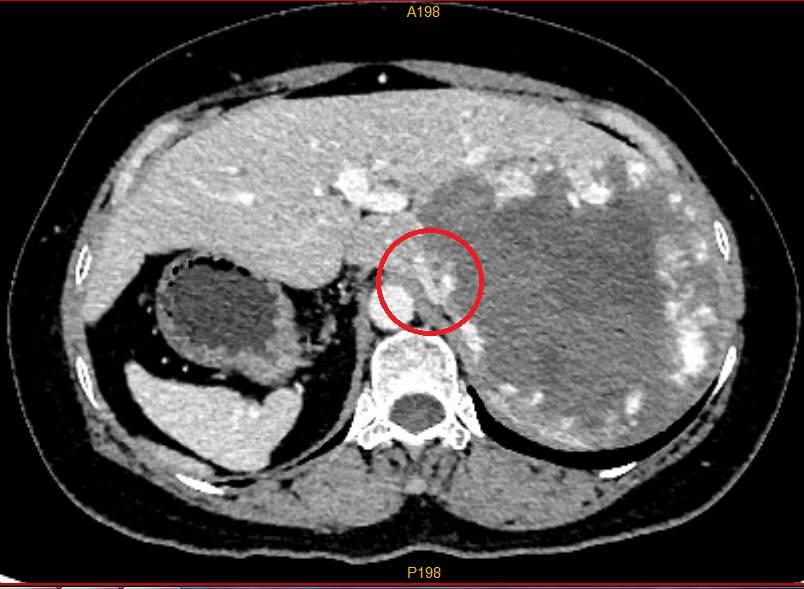

盧女士腹腔內臟完全相反,胃、脾在右邊,右肝在左邊,紅圈的下腔靜脈已被巨大血管瘤壓迫包繞。(互聯網)